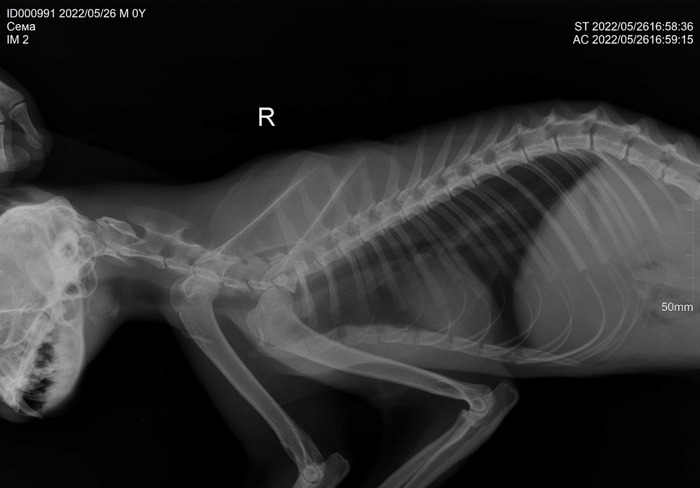

Живу в исламской республике нашей страны. Работаю врачом ветеринарным в двух клиниках. Доход для нашего региона нормальный. Не сказать что могу позволить себе все что заблагорассудится, но и жаловаться нет причин, акромя того что моя профессия тут не особо в почете. Ветеринар я.

В течении 10 лет я ездил на конференции, мастерклассы в надежде что когда то транспедикулярные фиксаторы, импланты надколенника, двойные остеотомии таза, мрт, кт, эндоскопические манипуляции будут востребованы у нас.

ПС: доход в основном на банальных процедурах ‐кастрации, абсцессы и вакцинации